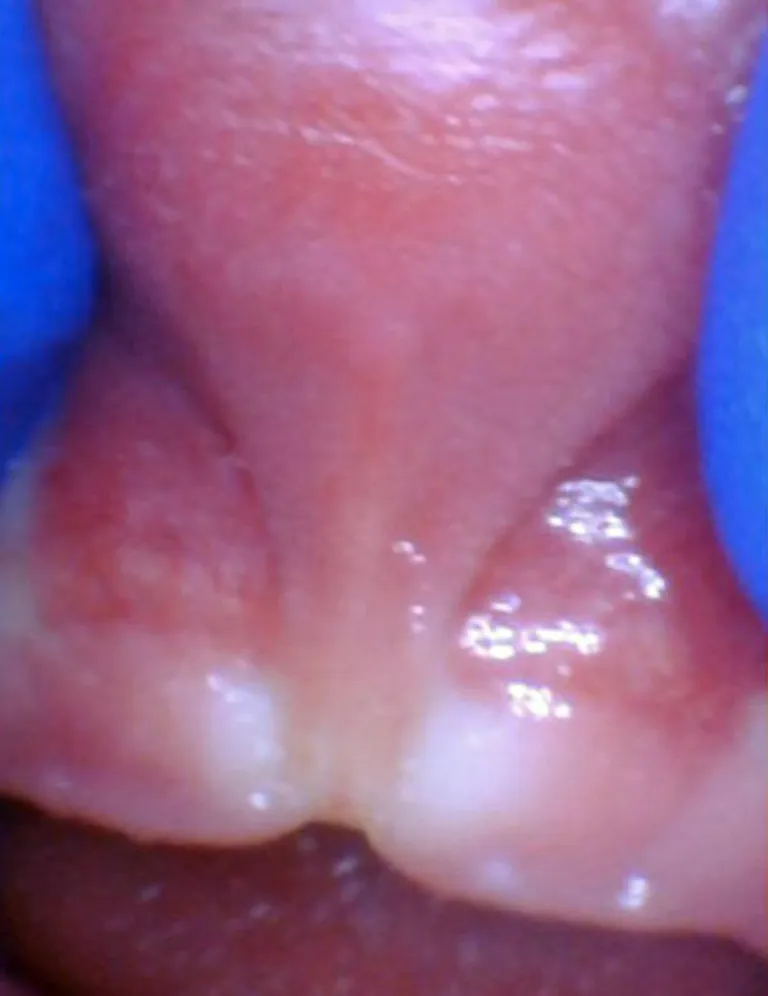

Enfant - Spectre de restrictions d'un FR lingual

Bébé - Spectre de restrictions d'un FR lingual